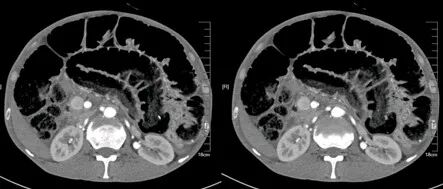

肾挫伤

肾挫伤是一种比较多见的肾损伤,肾组织损伤较轻,肾包膜和肾盂大多保持完整,肾实质内产生瘀血或血肿,并有少量血液流入肾盂导致血尿。肾挫伤在X线造影片上可不显示形态上的改变。一般均能自行愈合而不造成严重后果。